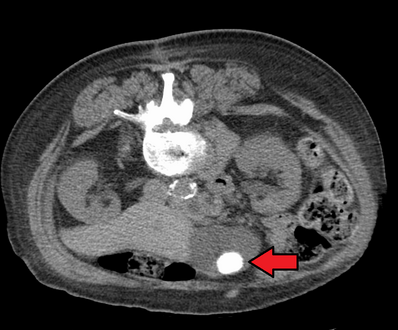

صور طبقية محوسبة لحصوات المرارة.

حصوة حجمها 1.9 سم في عنق المرارة وتؤدي إلى التهاب المرارة كما يظهر في الموجات فوق الصوتية. هناك سماكة في جدار المرارة بمقدار 4 ملم.